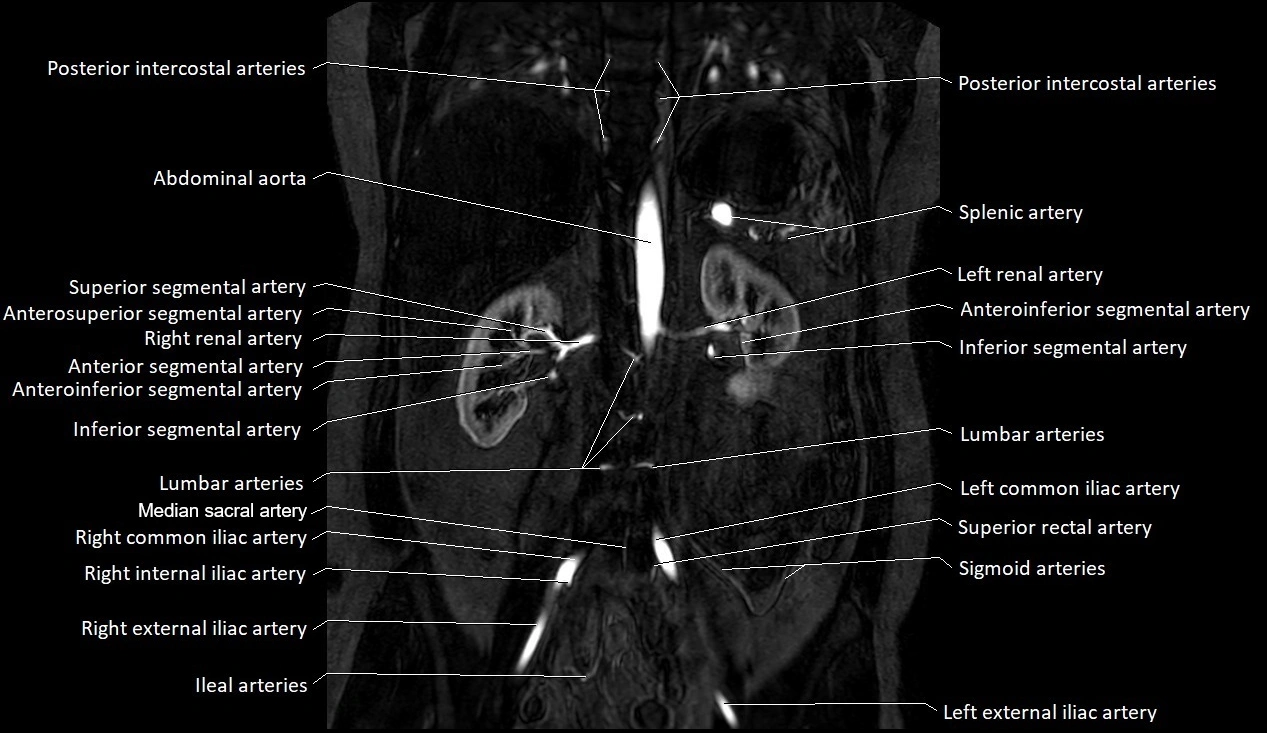

MRI images

image